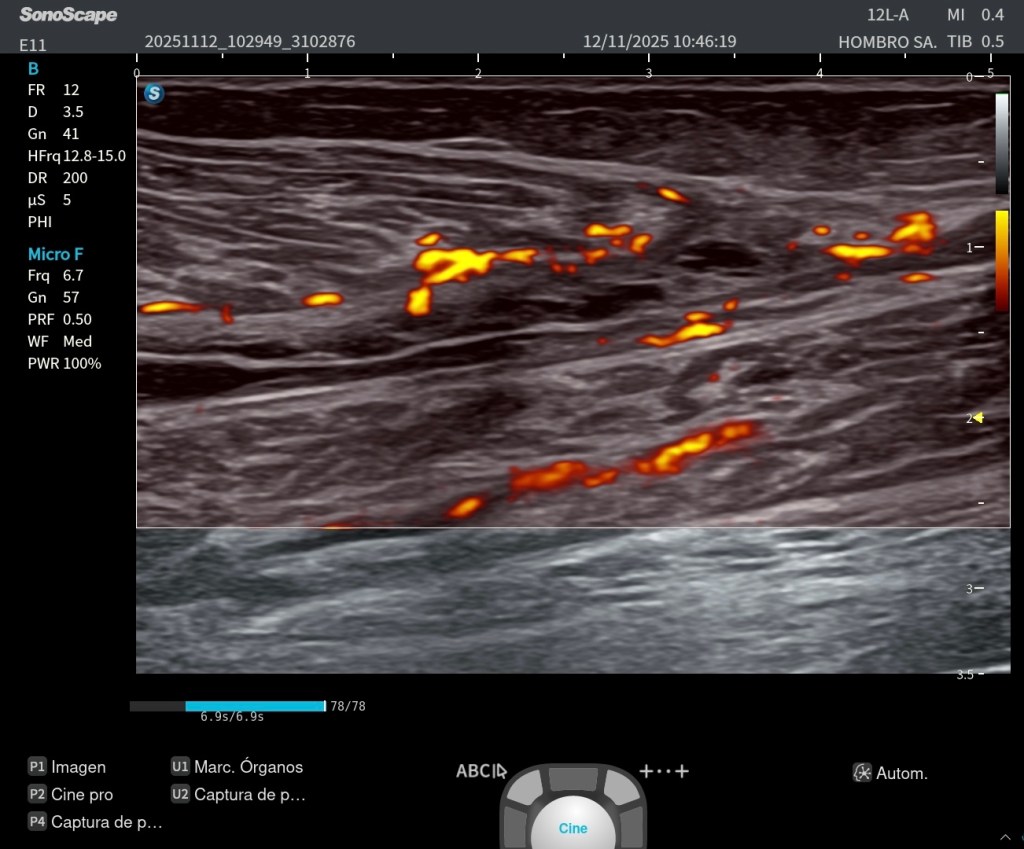

Pero hay un elemento especialmente relevante desde el punto de vista anatómico y ecográfico: el llamado triángulo arterial plantar. Este concepto, que se aprecia especialmente en la imagen con Doppler, está formado por la arteria plantar medial, la arteria plantar lateral y el propio arco plantar profundo. Más que una figura geométrica estricta, es una forma de entender la disposición vascular en este plano. Identificar este triángulo significa que estás exactamente donde debes estar.